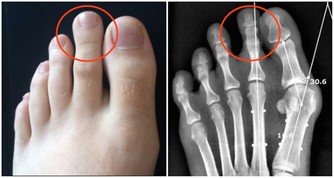

後來孩子說自己關節疼,喬女士認為生病了難免會覺得不舒服,自己感冒時也會覺得腰酸背痛的,於是安慰孩子沒關係,很快就會好的。直到她發現孩子身上莫名出現瘀青,牙齦還總是流血,她才意識到有點不正常。拿到報告單後她崩潰大哭,覺得是自己害了孩子,要不是自以為是拖這麼久,說不定孩子早就接受治療了。

醫生提醒:孩子貧血沒有精神、頻繁發燒降不下來、鼻腔牙齦莫名出血、關節疼痛水腫,這些都可能暗示白血病到來,若是經過用藥還沒有緩解,就不要再拖下去了,盡快就醫檢查。